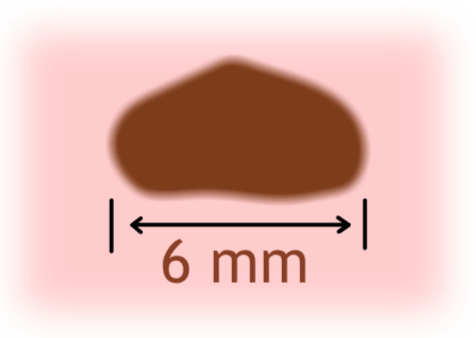

- D - Průměr (Diameter) - větší než 6 mm (jako guma na tužce).